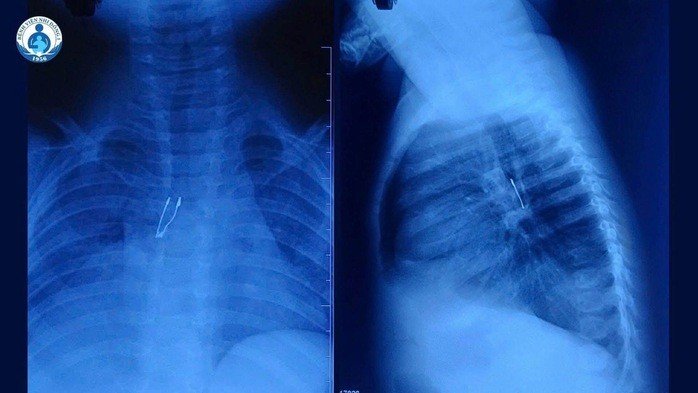

Vật thể được lấy ra là một chiếc bóng đèn LED với phần đuôi sắc nhọn, nằm sâu trong đường thở của trẻ, đe dọa trực tiếp đến tính mạng nếu không được xử lý kịp thời.

Bệnh nhi N.K.N (ngụ tại Đồng Tháp) nhập viện trong tình trạng ho kéo dài liên tục suốt hai ngày. Qua chẩn đoán hình ảnh tại tuyến dưới và kết quả kiểm tra chuyên sâu tại Bệnh viện Nhi Đồng 1, các bác sĩ phát hiện một dị vật cản quang nằm tại phế quản gốc phải. Tình trạng của bé tiến triển khá nghiêm trọng khi phổi phải bắt đầu có dấu hiệu xẹp không hoàn toàn và xuất hiện triệu chứng tràn khí trung thất. Điều đáng nói là gia đình hoàn toàn không hay biết trẻ đã hít phải vật gì và vào thời điểm nào.

Nhận định đây là ca cấp cứu phức tạp, BS Lý Phạm Hoàng Vinh cùng ê-kíp Khoa Tai mũi họng đã phối hợp liên chuyên khoa để tiến hành nội soi phế quản khẩn cấp. Quá trình can thiệp đối mặt với thử thách lớn do đặc thù của dị vật: chiếc đèn LED có phần đuôi bè ra và rất sắc. Trong điều kiện đường thở của trẻ 9 tháng tuổi vốn rất nhỏ hẹp, dị vật này cực kỳ dễ bị kẹt lại khi đi qua thanh quản hoặc gây rách niêm mạc. Các bác sĩ đã phải vô cùng tỉ mỉ, vừa xoay vừa điều chỉnh vị trí dị vật từng chút một để đưa ra ngoài an toàn. Thậm chí, đội ngũ Ngoại lồng ngực cũng được huy động vào tư thế sẵn sàng hỗ trợ nếu xảy ra biến chứng tràn khí màng phổi.

Sau nỗ lực bền bỉ của ê-kíp, chiếc đèn LED đã được gắp ra thành công trong sự nhẹ nhõm của gia đình và các y bác sĩ. Hiện tại, sức khỏe của bé N. đã ổn định, hô hấp bình thường, giảm ho rõ rệt và dự kiến sớm được xuất viện do không ghi nhận thương tổn hay biến chứng sau thủ thuật.